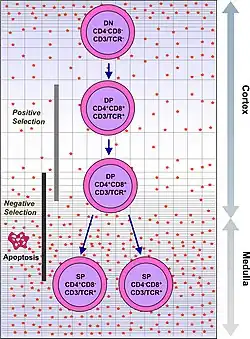

The thymus facilitates the maturation of T cells, an important part of the immune system providing cell-mediated immunity.[11] T cells begin as hematopoietic precursors from the bone-marrow, and migrate to the thymus, where they are referred to as thymocytes. In the thymus they undergo a process of maturation, which involves ensuring the cells react against antigens ("positive selection"), but that they do not react against antigens found on body tissue ("negative selection").[11] Once mature, T cells emigrate from the thymus to provide vital functions in the immune system.[11][12]

Each T cell has a distinct T cell receptor, suited to a specific substance, called an antigen.[12] Most T cell receptors bind to the major histocompatibility complex on cells of the body. The MHC presents an antigen to the T cell receptor, which becomes active if this matches the specific T cell receptor.[12] In order to be properly functional, a mature T cell needs to be able to bind to the MHC molecule ("positive selection"), and not to react against antigens that are actually from the tissues of body ("negative selection").[12] Positive selection occurs in the cortex and negative selection occurs in the medulla of the thymus.[13] After this process T cells that have survived leave the thymus, regulated by sphingosine-1-phosphate.[13] Further maturation occurs in the peripheral circulation.[13] Some of this is because of hormones and cytokines secreted by cells within the thymus, including thymulin, thymopoietin, and thymosins.[4]

Positive selection

T cells have distinct T cell receptors. These distinct receptors are formed by process of V(D)J recombination gene rearrangement stimulated by RAG1 and RAG2 genes.[13] This process is error-prone, and some thymocytes fail to make functional T-cell receptors, whereas other thymocytes make T-cell receptors that are autoreactive.[14] If a functional T cell receptor is formed, the thymocyte will begin to express simultaneously the cell surface proteins CD4 and CD8.[13]

The survival and nature of the T cell then depends on its interaction with surrounding thymic epithelial cells. Here, the T cell receptor interacts with the MHC molecules on the surface of epithelial cells.[13] A T cell with a receptor that doesn't react, or reacts weakly will die by apoptosis. A T cell that does react will survive and proliferate.[13] A mature T cell expresses only CD4 or CD8, but not both.[12] This depends on the strength of binding between the TCR and MHC class 1 or class 2.[13] A T cell receptor that binds mostly to MHC class I tends to produce a mature "cytotoxic" CD8 positive T cell; a T cell receptor that binds mostly to MHC class II tends to produce a CD4 positive T cell.[14]

Negative selection

T cells that attack the body's own proteins are eliminated in the thymus, called "negative selection".[12] Epithelial cells in the medulla and dendritic cells in the thymus express major proteins from elsewhere in the body.[13] The gene that stimulates this is AIRE.[12][13] Thymocytes that react strongly to self antigens do not survive, and die by apoptosis.[12][13] Some CD4 positive T cells exposed to self antigens persist as T regulatory cells.[12]